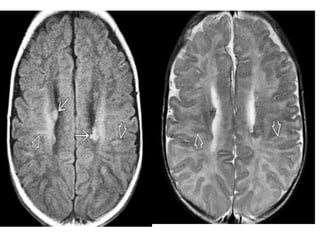

• #32 More cephalad scan shows additional hyperintense subependymal nodules as well as multiple hyperintense radial bands extending outward from the lateral ventricles. More cephalad T2WI shows that the thickened radial bands are hypointense relative to the unmyelinated white matter. tubers appear as thickened hyperintense cortex compared to the underlying unmyelinated WM on T1WI and become moderately hypointense on T2WI. "Streaky" linear or wedge-shaped T2/FLAIR hyperintense bands may extend from the tuber all the way through the WM to the ventricular ependyma

• #34 T2WI shows that the WM is largely unmyelinated. The SENs are isointense with gray matter. Cortical tubers have poor GM-WM delineation.